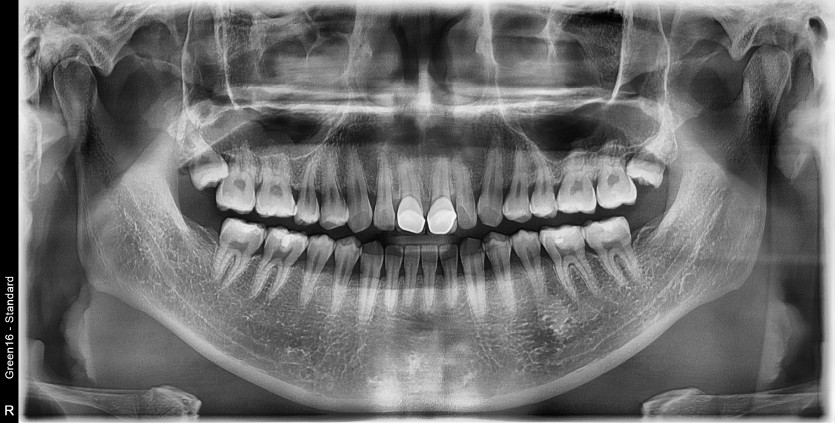

#18 사랑니 발치

구강 외과 전문의가 당일 발치했습니다.